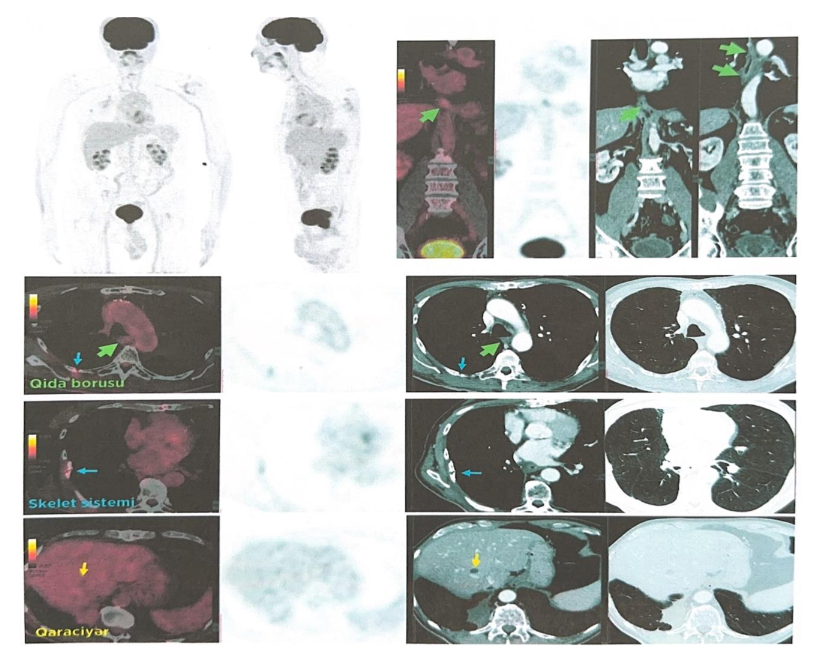

In 2020, imaging detected a new intravesical lesion. The patient underwent transurethral resection of the bladder tumor (TURBT), which revealed urothelial carcinoma. He subsequently received intravesical Bacillus Calmette–Guérin (BCG) therapy from January 29 to February 27, 2020. Post-treatment ^18F-FDG PET/CT demonstrated no evidence of residual disease.

FOLLOW-UP AND LONG-TERM OUTCOME

Since completing definitive therapy, the patient has been monitored annually with whole-body PET/CT.

During follow-up, a secondary malignancy was detected and treated successfully. Subsequent imaging confirmed the absence of residual or recurrent bladder disease.

To date, there is no evidence of recurrence of either the primary pulmonary adenocarcinoma or the secondary bladder carcinoma. More than 10 years after initial diagnosis, the patient remains clinically stable and continues maintenance therapy with Erlotinib (150 mg/day). Annual whole-body PET/CT imaging continues to demonstrate complete remission with no evidence of disease recurrence or progression.